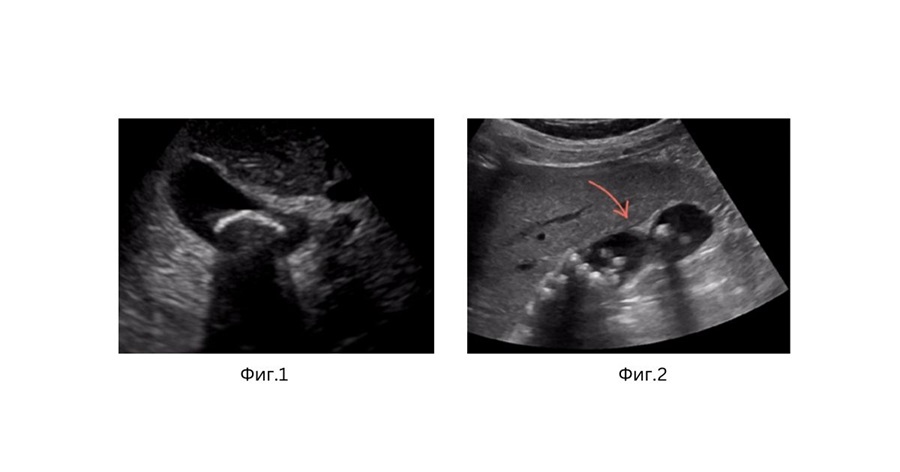

Не всеки пациент с камъни в жлъчния мехур има нужда от операция. Но категорично я препоръчвам на пациенти със следните симптоми: повтарящи се болки в дясното подребрие (жлъчни колики и жлъчни кризи), при наличие на камъни с висок риск от усложнения (единични големи конкременти – фиг. 1, множество конкременти в мехура – фиг. 2, с полипи и др.), при пациенти след проведена ERCP с отстраняване на камъни от жлъчните канали и остатъчна калкулоза на жлъчния мехур.